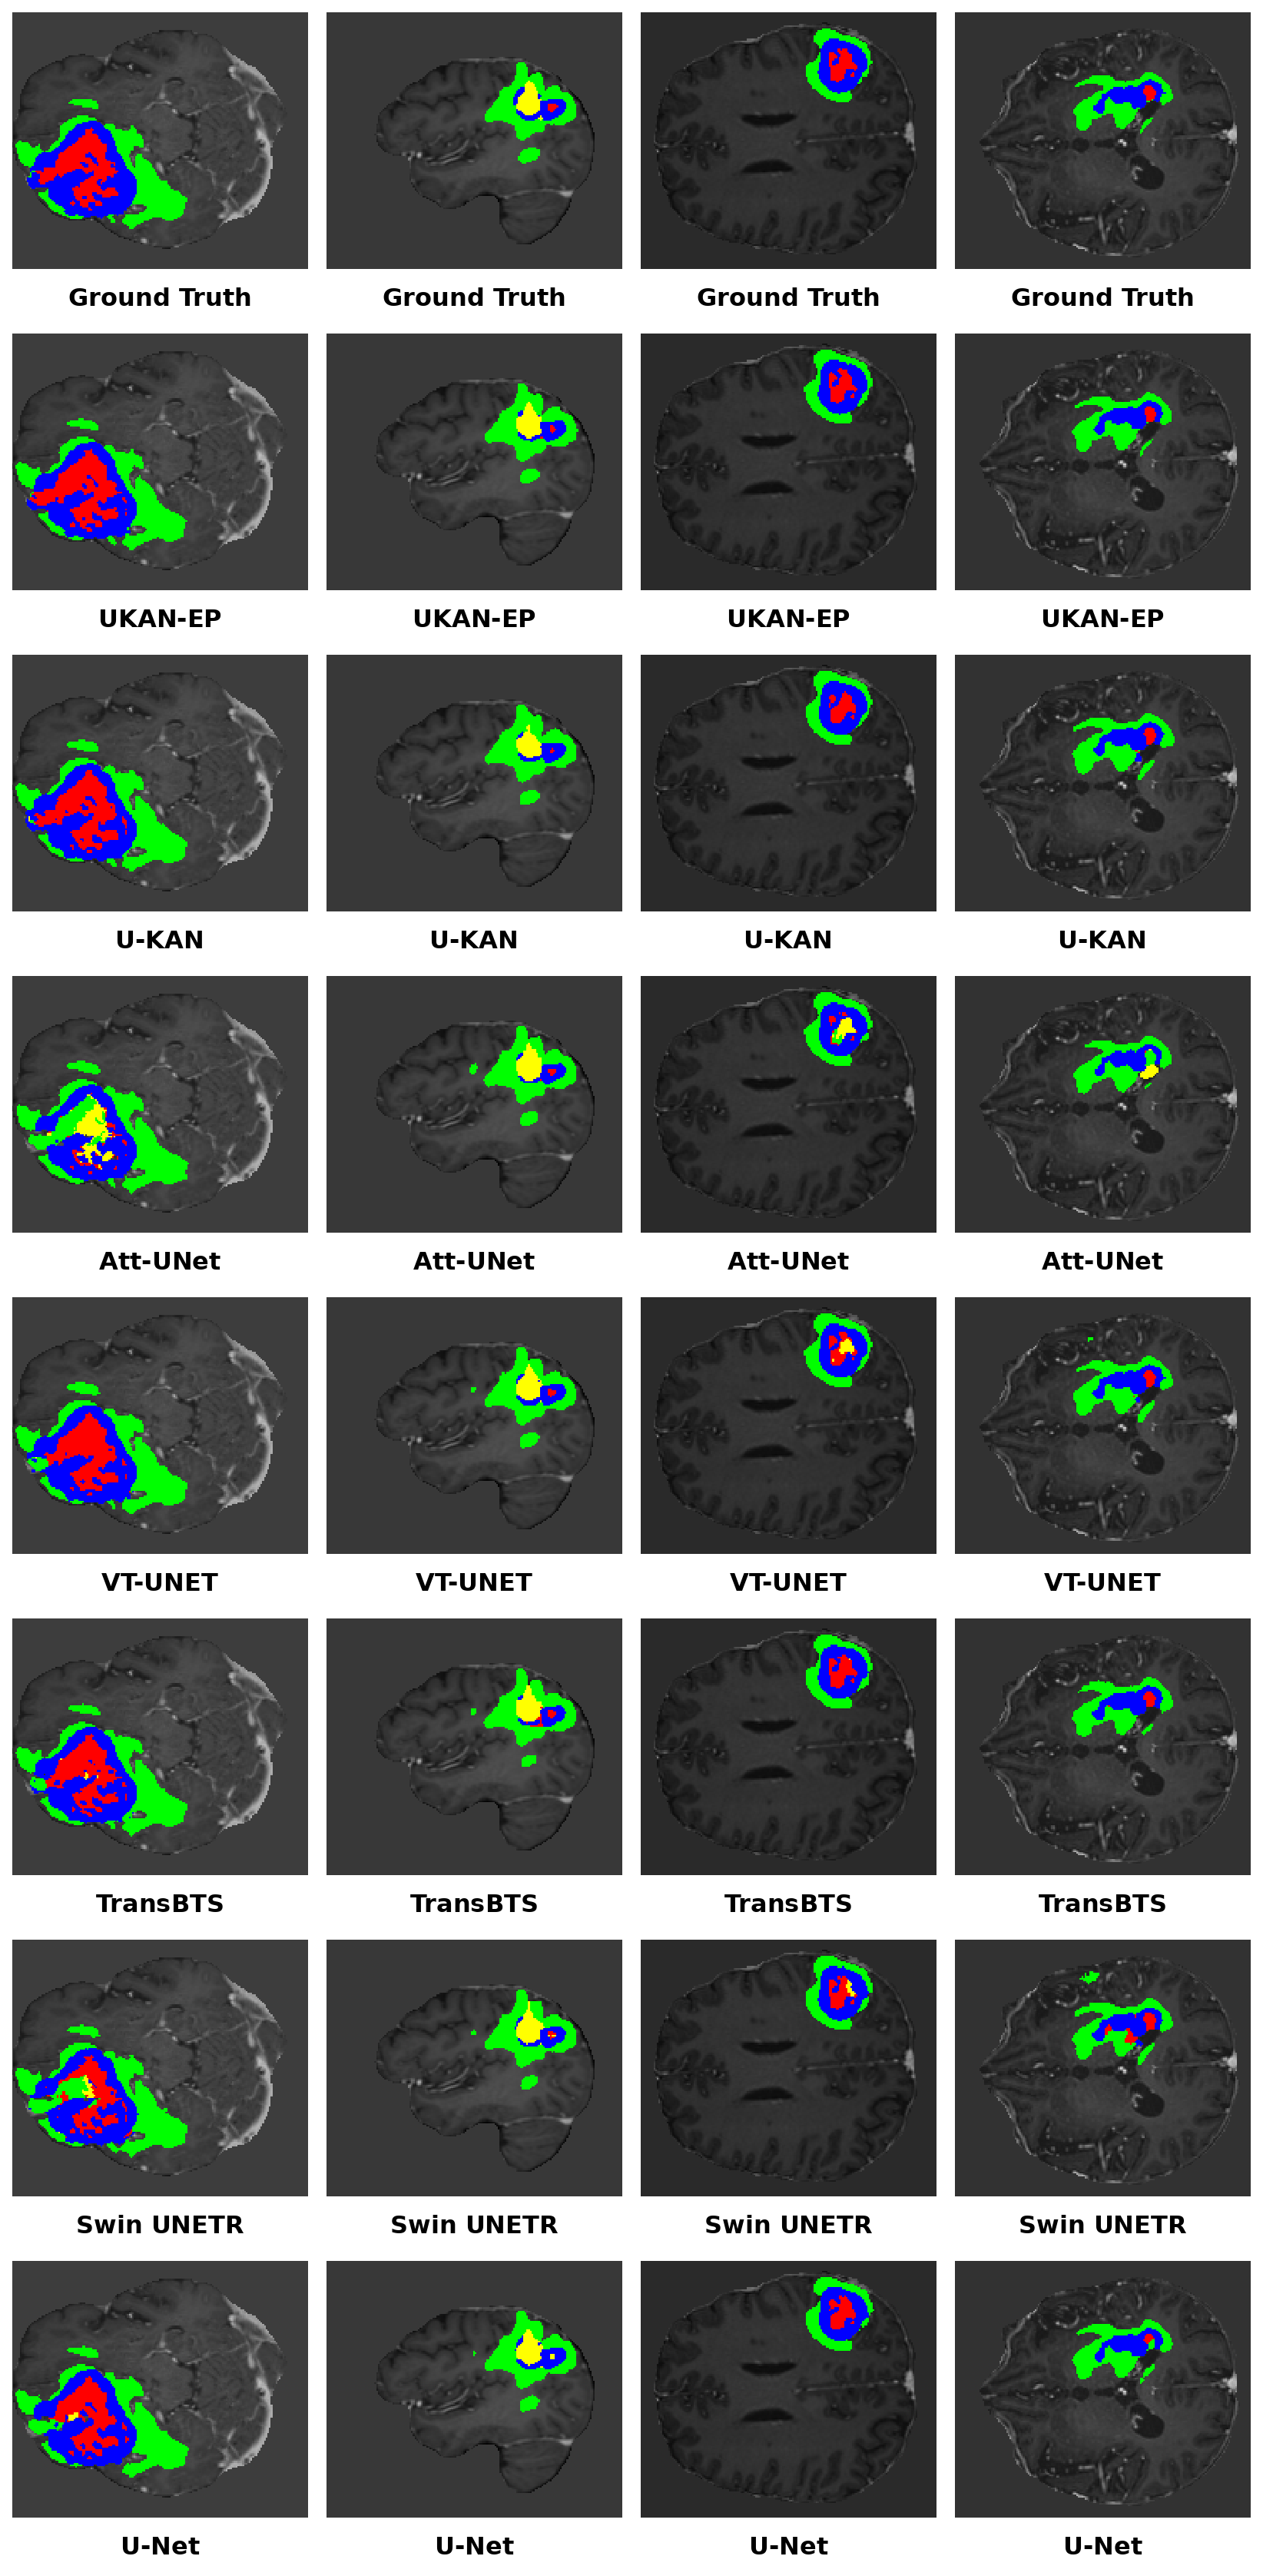

The segmentation results are illustrated in Figure 3. This figure presents representative examples from four test cases, including two from the challenge dataset and two from the post-challenge dataset. The visual comparison demonstrates that UKAN-EP achieves more complete and smoother tumor delineations across the NETC, SNFH, ET, and RC regions, exhibiting superior boundary continuity and structural consistency. Swin UNETR tends to produce fragmented segmentation results, likely due to its heavy encoder design, which leads to overfitting during feature extraction and limited generalization on small 3D datasets. Att-Unet shows similar behavior, especially in the NETC region, where its attention mechanism may drift under complex lesion morphology or low image contrast, resulting in incomplete localization. U-Net and TransBTS demonstrate suboptimal performance in fine boundary delineation, possibly because their feature fusion stages oversmooth high-frequency spatial details, reducing sensitivity to subtle structural variations. VT-UNet exhibits a high misclassification rate, indicating that while its global modeling capability is strong, it lacks sufficient local contextual constraints. Although U-KAN and UKAN-EP perform comparably overall, the former shows slightly inferior segmentation and produces more misclassifications. In contrast, UKAN-EP generates sharper lesion boundaries and effectively suppresses spurious predictions, highlighting the contributions of the PFA module in maintaining spatial consistency and the ECA module in refining feature weighting and channel selection, thereby achieving a balanced integration of global perception and local discrimination. These qualitative observations are consistent with the quantitative improvements reported in Tables 24, confirming the robustness and boundary precision of the proposed UKAN-EP.

Refer to caption

Figure 3: Example segmentation results for four BraTS-GLI test cases from the 2024 BraTS Challenge dataset (first two columns) and the post-Challenge dataset (last two columns). Red is NETC, green is SNFH, blue is ET, and yellow is RC.